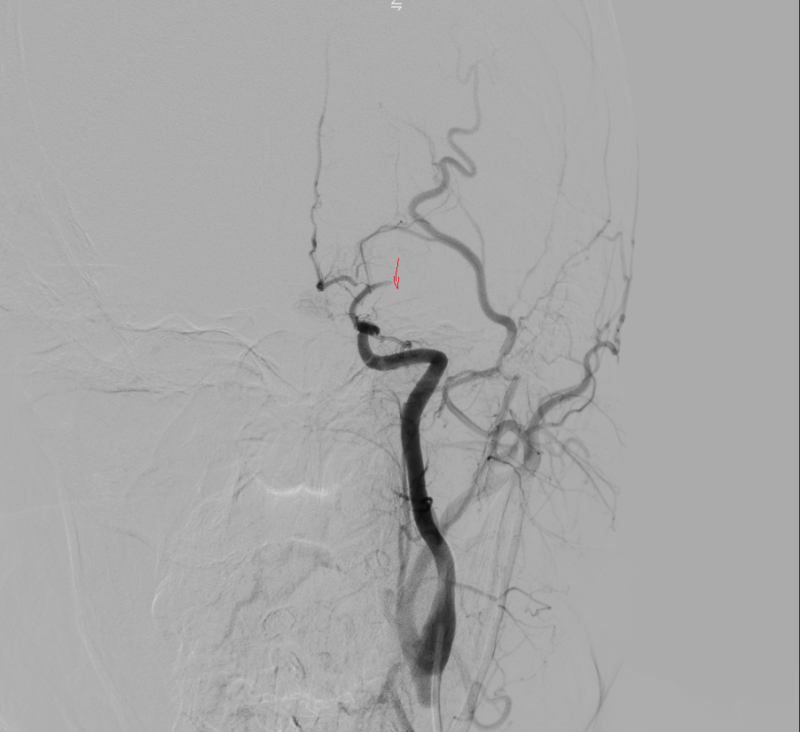

Kết quả chụp DSA xác định tắc động mạch não giữa trái đoạn M1 do hẹp nặng. Kíp can thiệp đã tiến hành nong bóng tái thông mạch máu, khôi phục dòng chảy lên não thành công.

Hình ảnh: Chụp DSA trước can thiệp thấy tắc M1 trái